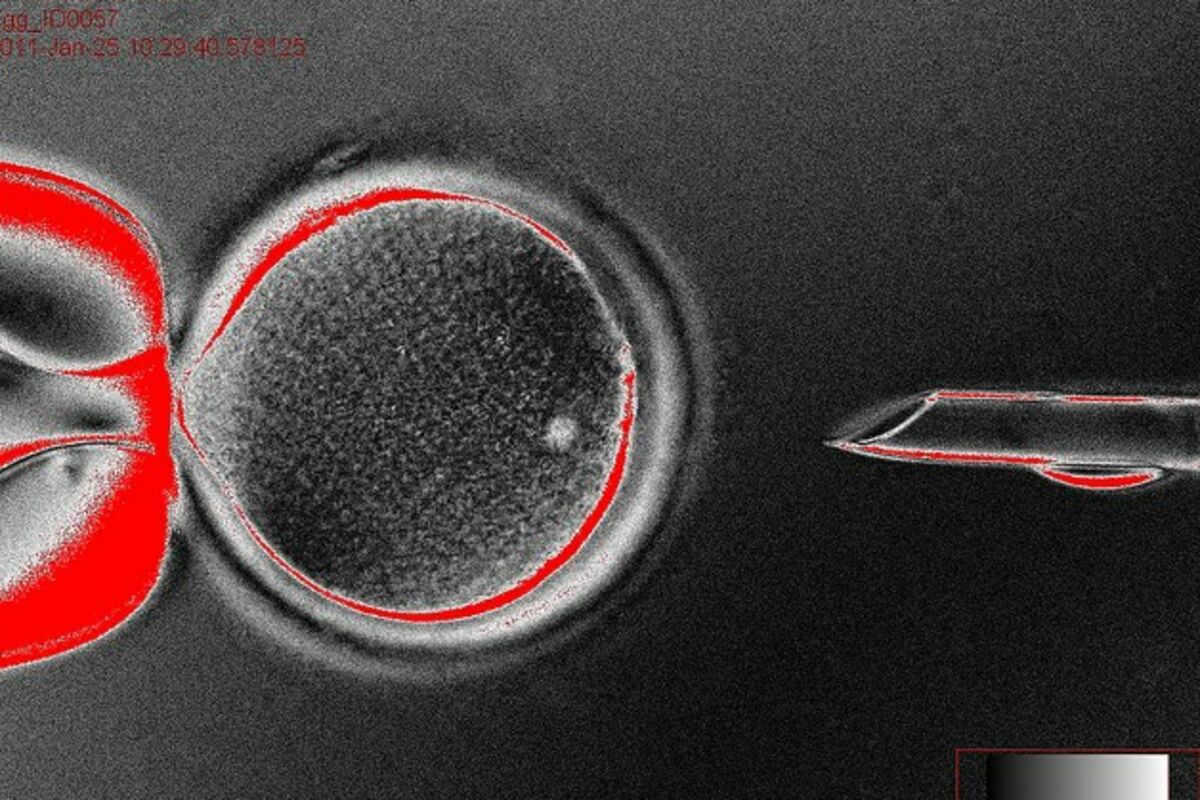

Matične ćelije, Foto: University of oregon

Transfer matičnih ćelija koštane srži u oštećenje kičmene moždine izvodi se tako što se matične ćelije izoluju iz koštane srži, nakon čega se pripremaju i ubrizgavaju na mjesto oštećenja.